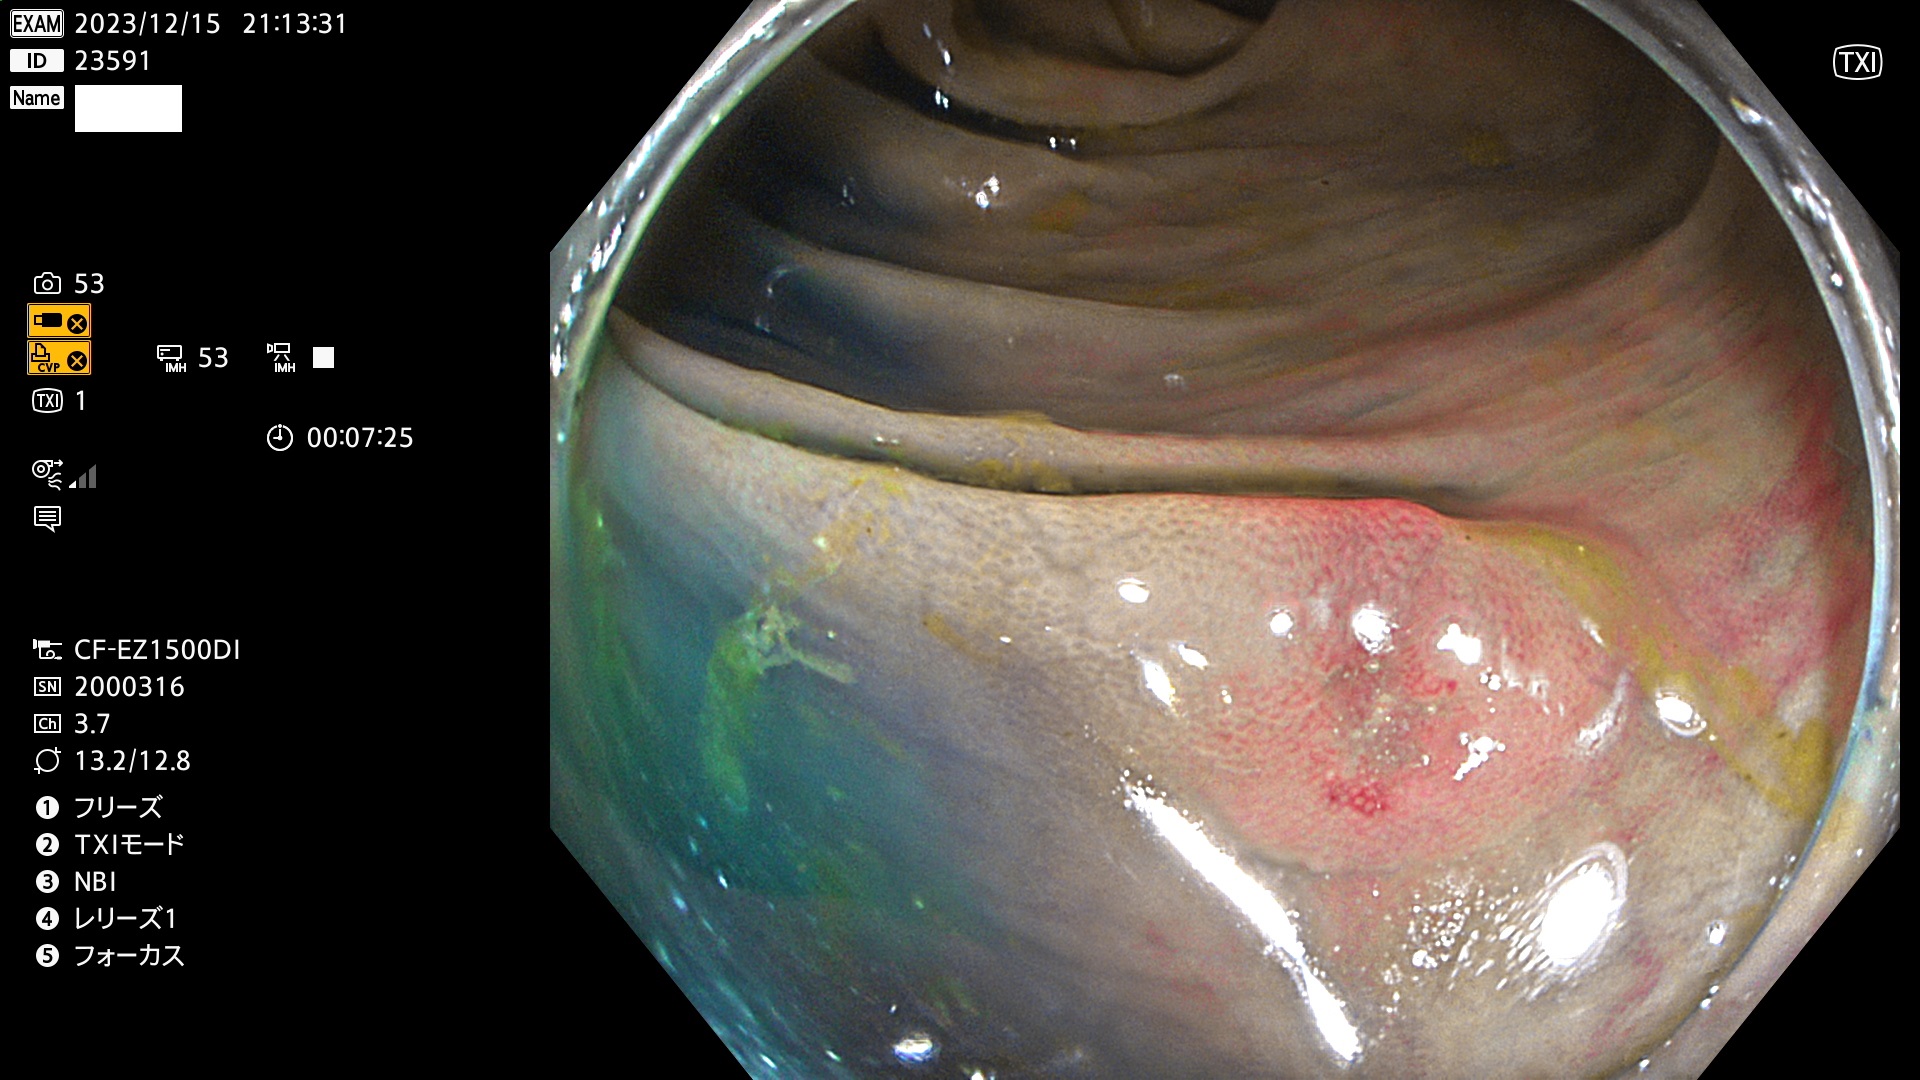

以下は当院で経験した「ビランと鑑別の難しいUc型腺腫」です(全て、病理で腺腫を確認済み)。

このような病変は表面を拡大観察しても診断は不可能であり、現在の内視鏡診断の「限界を超えた病変」と言えます。現実的な対策は「典型的なビランと異なる」と感じたら、「コールド法で積極的に切除する」ことと考えます。もちろん「結局はビランだった(不要な過剰切除だった)」ということもあります。しかしコールド法なら重篤な合併症は稀であり、医師は切除を躊躇すべきではないと考えます。